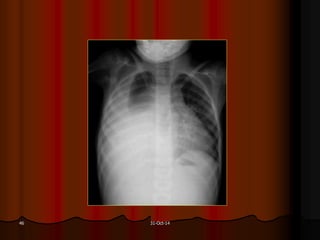

AÙP-XE THUØY LÖÔÕI PHOÅI (T)

October 31, 2014 AÙP-XETHUØY LÖÔÕI PHOÅI (T)